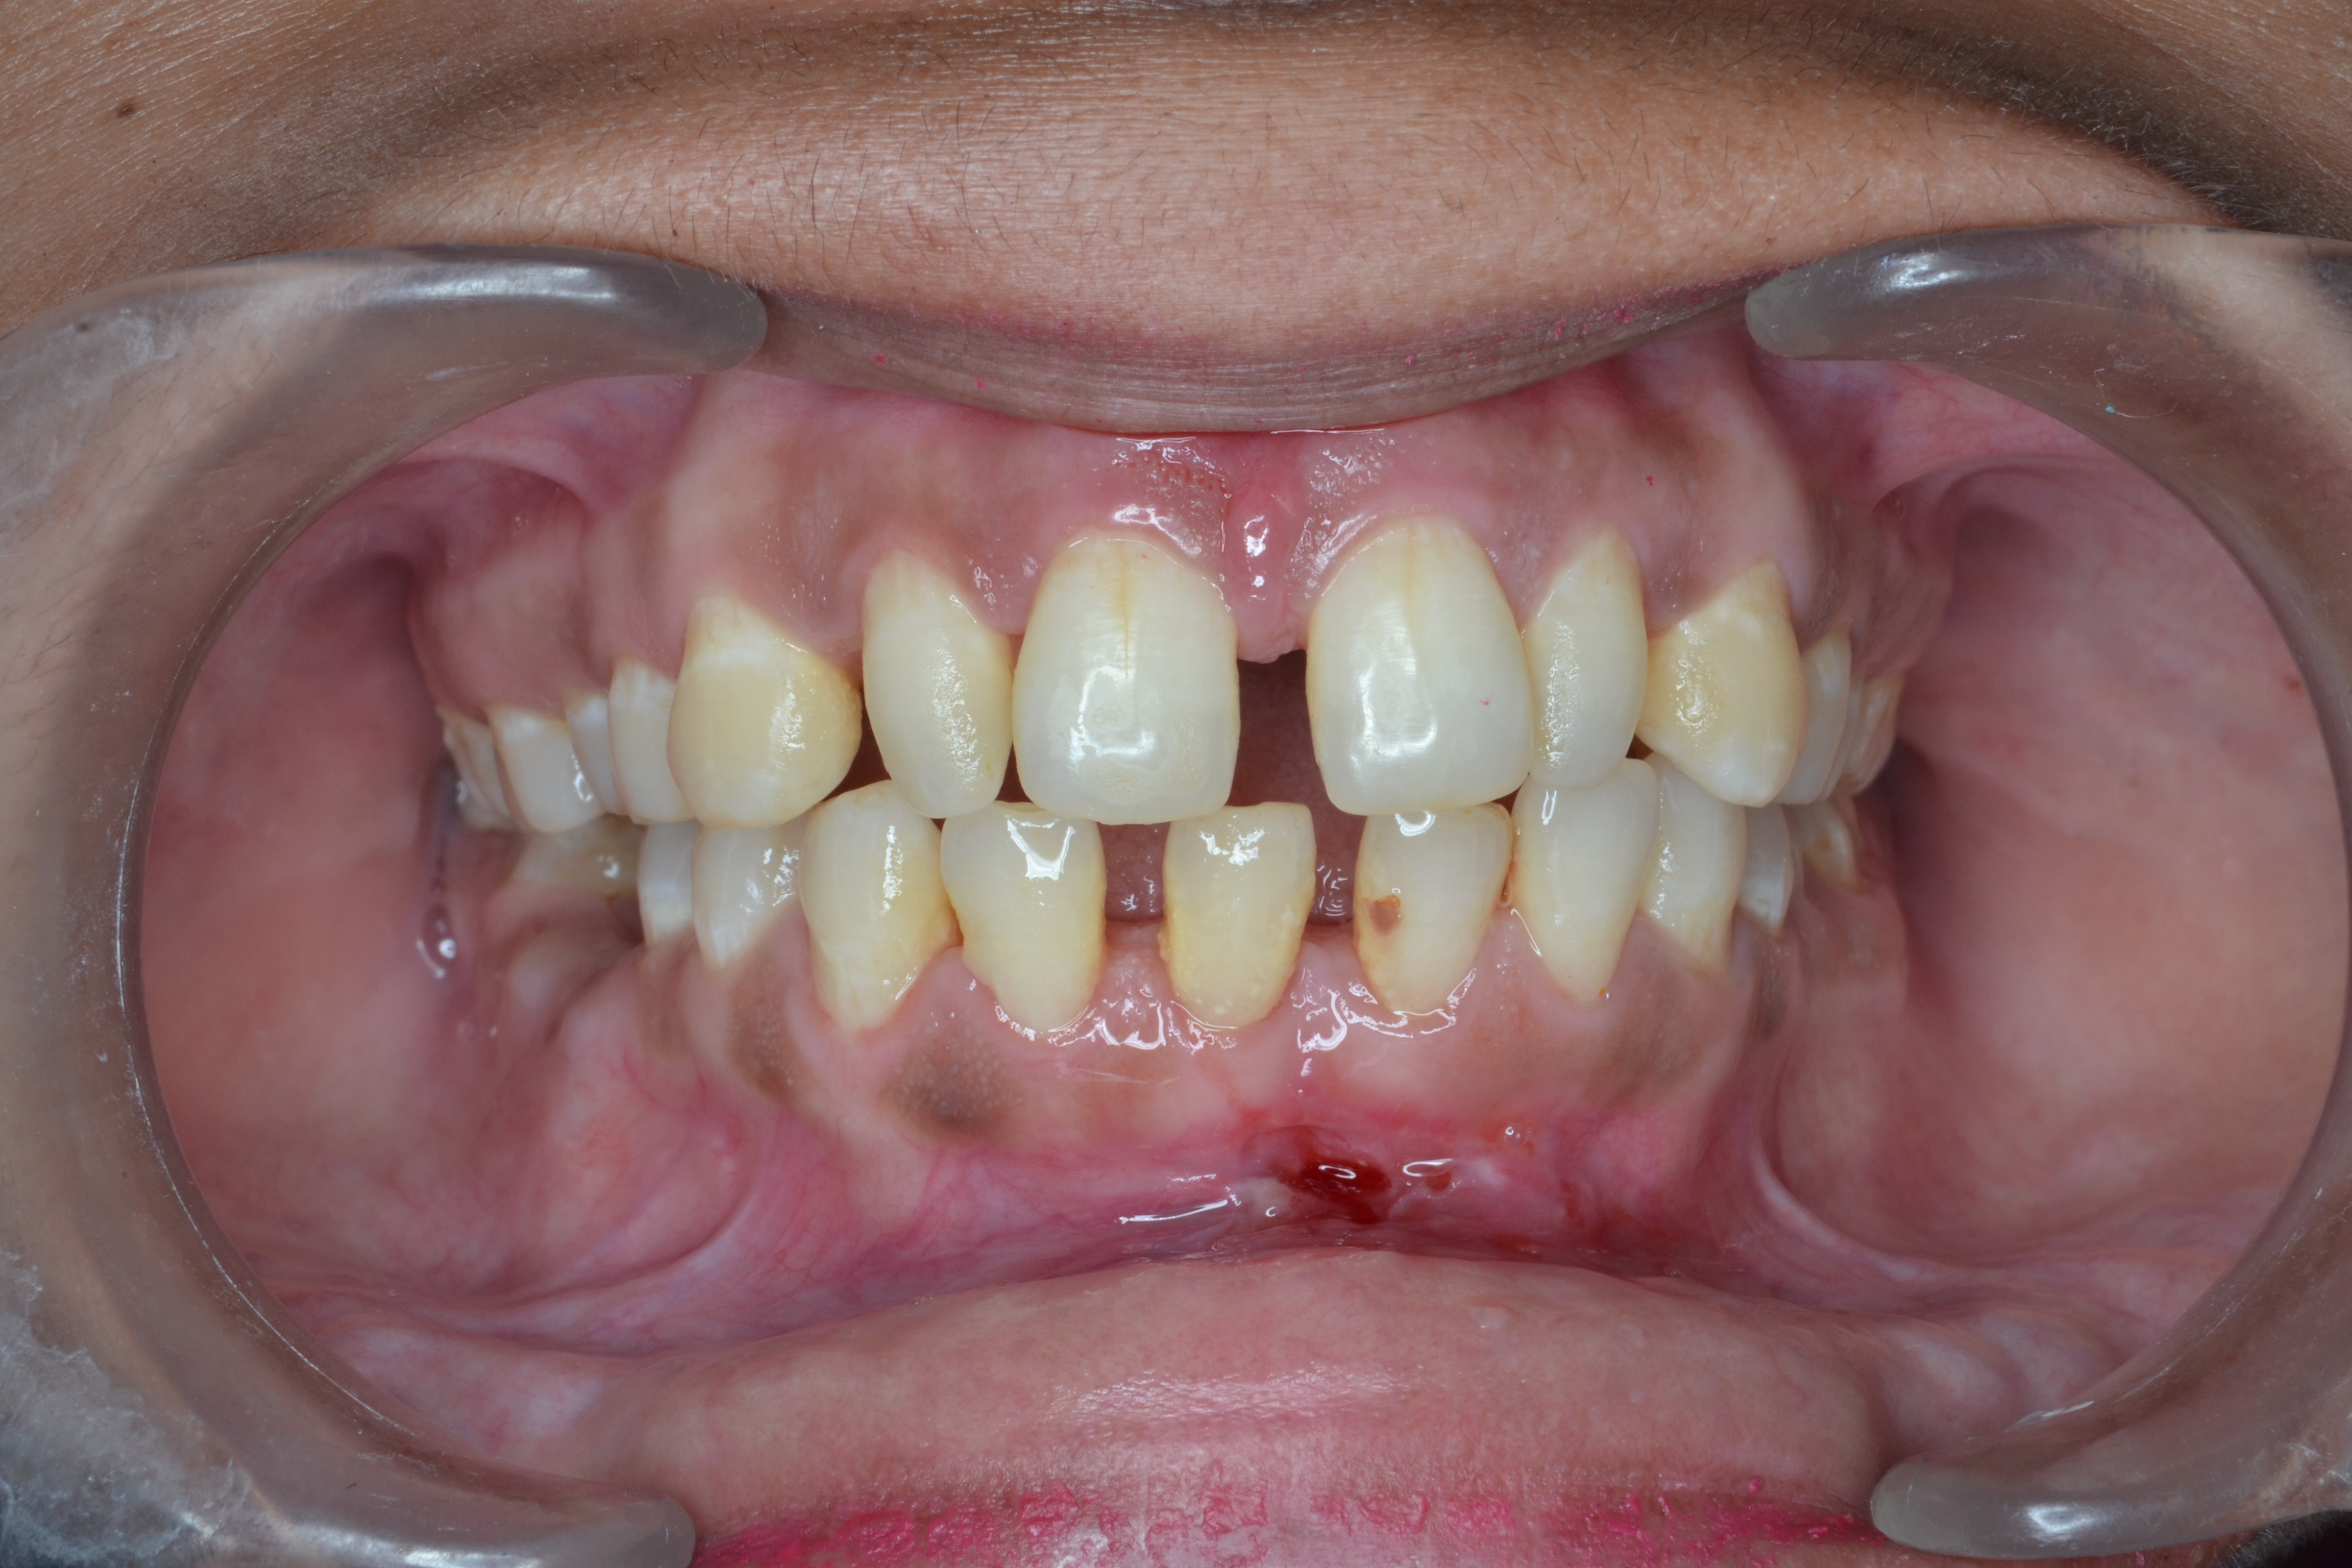

Sairam dental care located in Dharmapuri, with Leading Dentist In Oddapatti, is the Dental Hospital with exclusive root canal, Braces & Invisalign center. Led by renowned Drs Raghuraaman ( Periodontist) and Nivetha Raghuraaman ( Orthodontist) Sairam dental care offers gum treatment with expertise in laser, root canal treatment and digital smile correction with advanced technology aim to focus on aesthetics, comfort and precision. The clinic also specializes in Invisalign treatment, digital smile makeover, laser gum care, dental implants, root canal therapy, extractions and full-mouth rehabilitation blending compassionate care and clinical excellence.